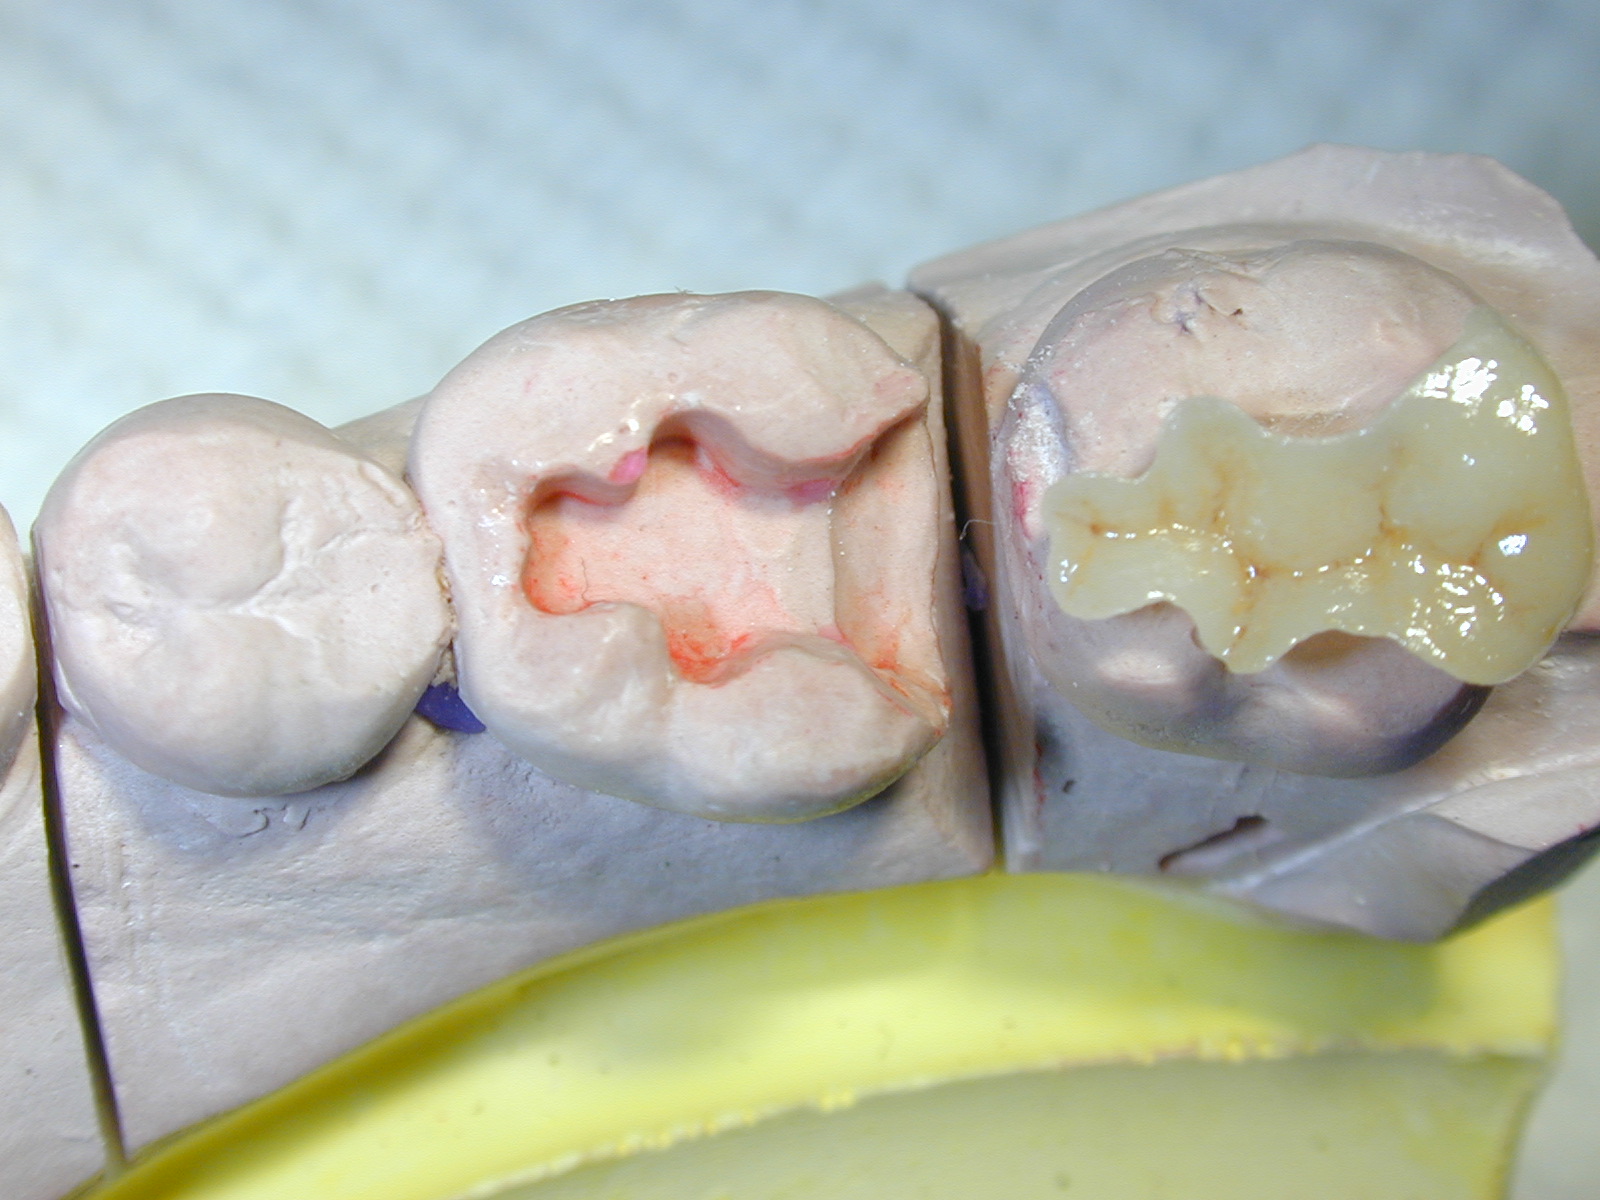

取相同的模型鑄造一個瓷牙嵌體

放入模型

放入牙齒